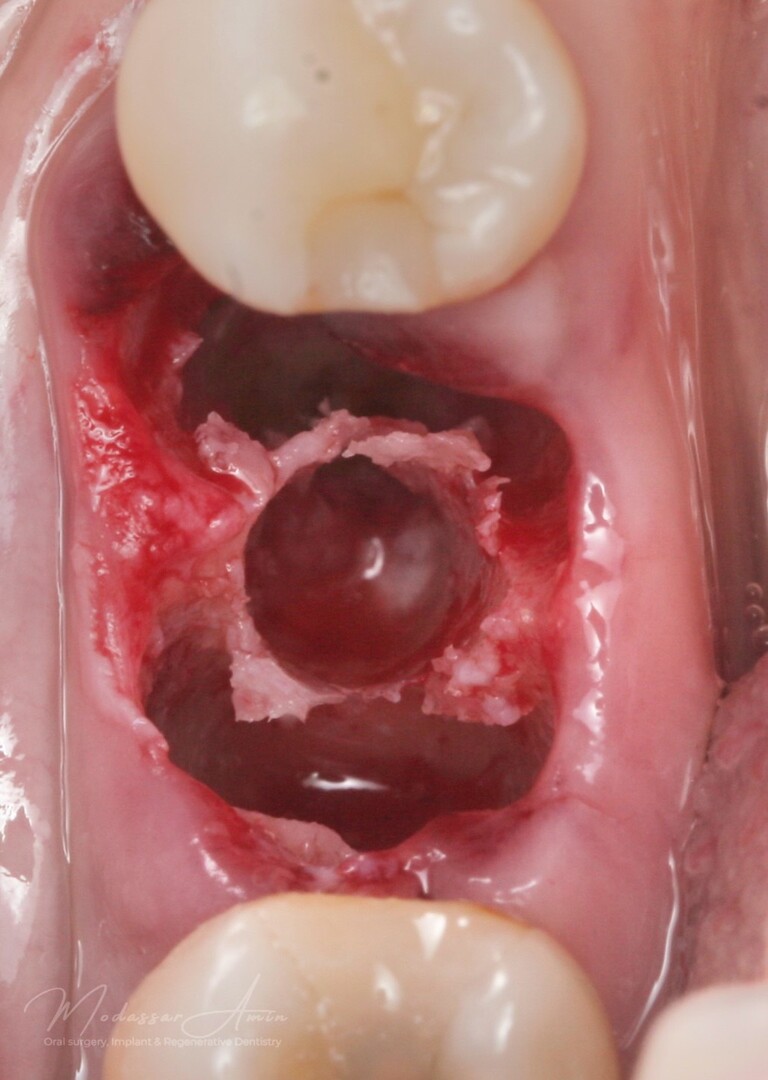

Septum ekspandert

God primær stabilitet på 40+ ncm